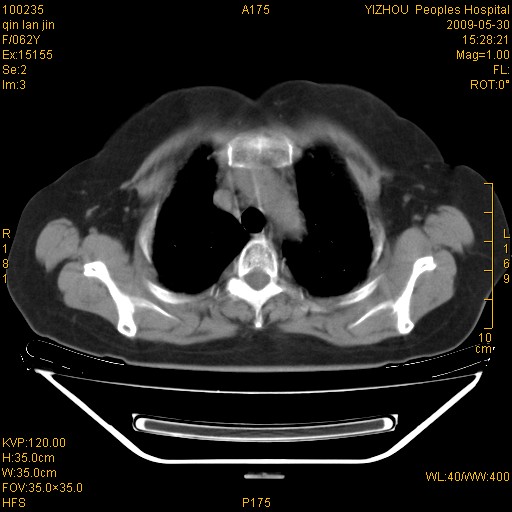

标题: CT20268:肺泡癌?间质性肺炎? [打印本页]

标题: CT20268:肺泡癌?间质性肺炎?

女,62岁,近二年经常咳嗽,近二个月,消瘦、乏力。

纵隔淋巴结大,须排外癌性淋巴管炎